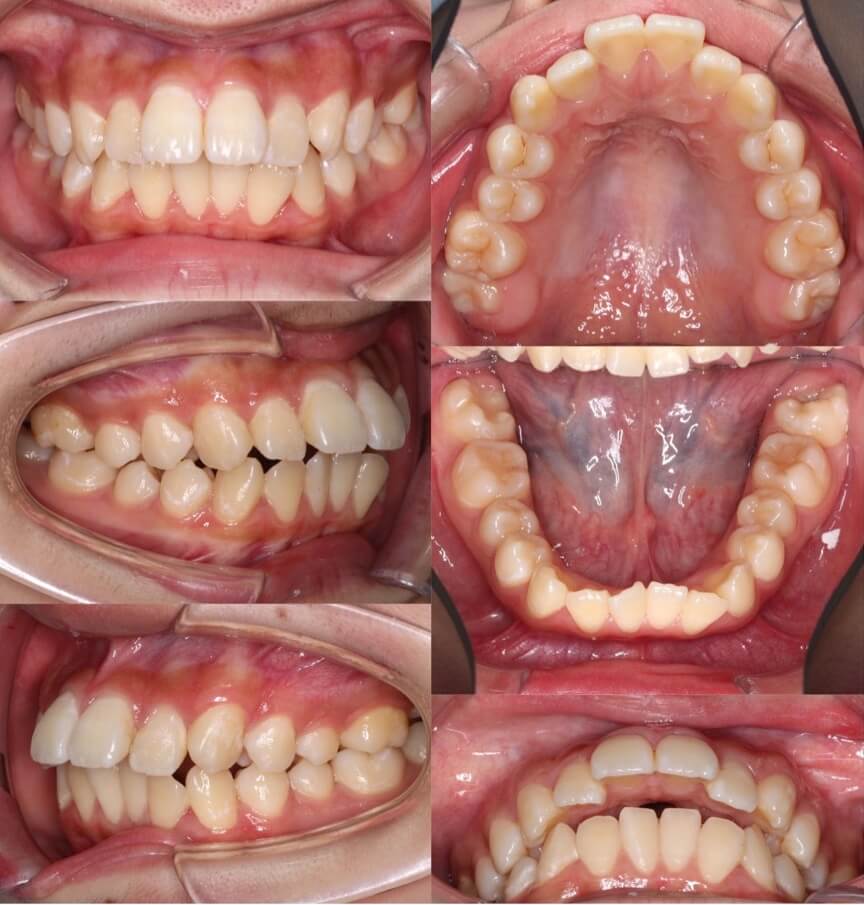

「美容目的にはリスクが伴う」

20代女性・マウスピース型装置・美容改善型

上の前歯の角度もE-lineも悪くはないのですが、患者さんは横顔での口元の突出感を改善したいということで、マウスピース型装置にて上下小臼歯抜歯矯正治療を行いました。美容目的要素が強くなるため、ほうれい線が深くなったり、ブラックとライアングルが増えるリスクについては事前によく説明しています。治療結果は前歯の後方移動量に対して横顔の変化量は少なめとなり、ちょうど良い形になりました。

<治療シミュレーション>

慎重に犬歯と前歯を後方移動させる。奥歯の多少の前方移動は許容できるため、小さめのアタッチメントを設置。

※マウスピース型カスタムメイド矯正歯科装置は完成物薬機法対象外の矯正装置であり、医薬品副作用被害救済制度の対象とはならない可能性があります。

<症例概要> 難易度:★★★☆☆

主訴:出っ歯・横顔の突出

年齢・性別:30代女性

住まい:千葉県船橋市

症状:軽度叢生・下顎前歯唇側傾斜

治療方針:抜歯空隙の閉鎖(中等度固定)

治療装置:マウスピース型矯正装置(アライナー装置)

抜歯:上下左右4番(計4本)

治療期間:1年6か月

アライナー枚数:47+30ステージ

リテーナー:上下クリアタイプ+フィックスタイプ

治療費用:990,000(税込)

代表的副作用:痛み・治療後の後戻り・歯根吸収・歯髄壊死・歯肉退縮